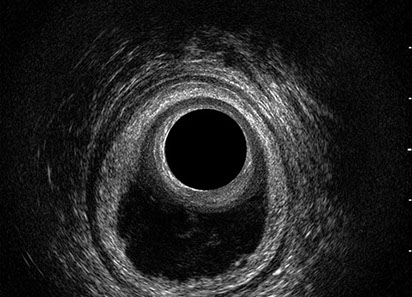

L’ecografia transanale è un esame diagnostico per immagini che consiste nell’introduzione di un trasduttore ad ultrasuoni. Le immagini qualitativamente migliori del canale anale sono ottenute usando un trasduttore rotante, montato in un manipolo rigido, che fornisce un’immagine a 360°. Con le apparecchiature più moderne è anche possibile ottenere immagini tridimensionali.

L’ecografia transanale permette di distinguere la sottomucosa che riveste il canale anale, lo sfintere anale interno, e lo sfintere anale esterno.

Le principali indicazioni all’esecuzione di tale esame sono lo studio dell’integrità delle strutture muscolari nei casi di incontinenza fecale, lo studio topografico dei processi settici perianali (ascessi e fistole) e lo studio dei processi proliferativi epiteliali (carcinoma anale).

Proctal dispone di apparecchiatura per ecografia endoanale 3D con sonda rotante.